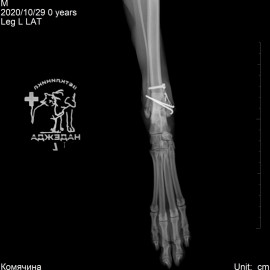

Рентгенологический снимок после проведенной операции.